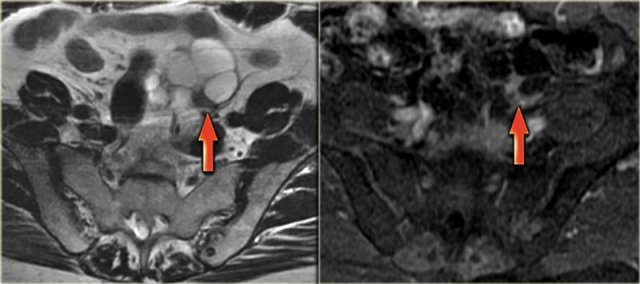

Corpus luteum cyst at MRI: an axial T2-weighted image demonstrating an involuting corpus luteum cyst (arrow).

This is a normal finding.

The right ovary is also normal.